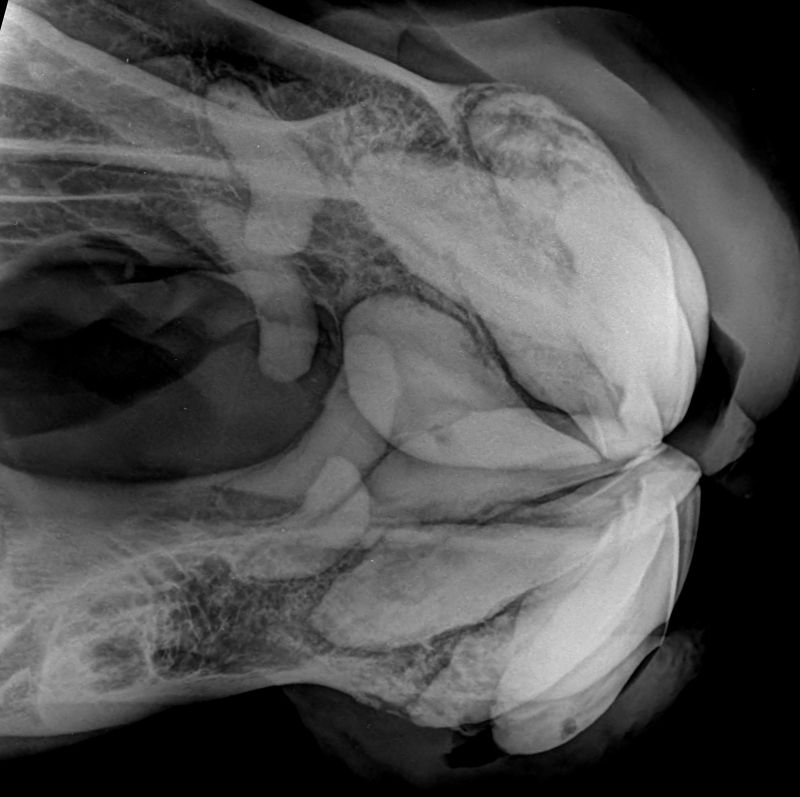

Röntgen Schräg

Extraktionstag Schrägaufnahme